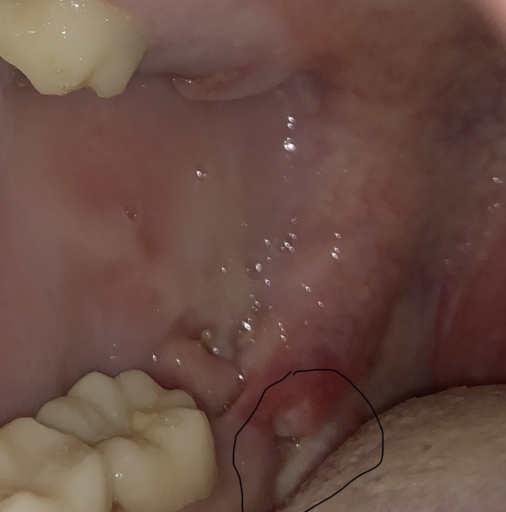

Why is there a bone or tooth coming out of my extraction site?

I had my wisdom teeth extracted 2 weeks ago, and the pain seemed to go away until about a week ago. At first, I didn't see the cause of the pain, but earlier today, I realized that there is something white growing out of my gum. I can't tell if it is a tooth or a bone. What should I do? I've read that they usually fall out on their own, or enter the blood stream, but I'm not sure.

Sometimes when a tooth is removed, the bone that was between the roots is no longer needed and breaks off. It will usually work itself out of the tissue, similar to a splinter. If it becomes uncomfortable, it can easily be removed from the tissue by your dentist. It will not enter the bloodstream and if it is swallowed should not cause any problems until it is discarded on it's own.